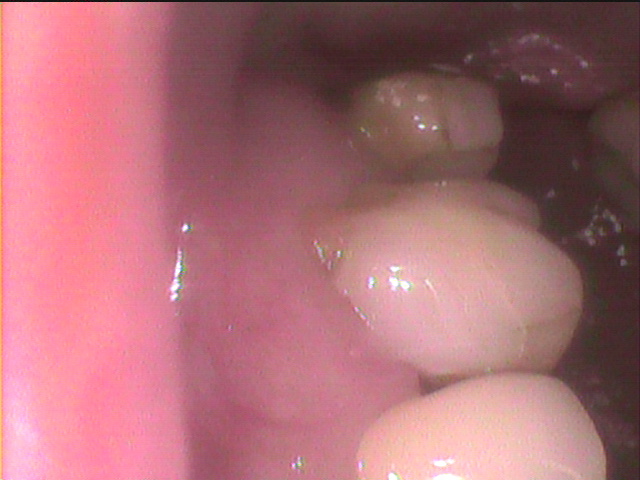

一連の並んだ歯が痛い場合

左の上が痛いという例

手前はジルコニアで修復してありますが

奥の大臼歯の2本の歯根が露出しています。

こういった場合には、いろいろな検査 試験をして

症状の強い部分から、処理をすべきです。

検討もしないで、神経を処理して

根管治療に持ち込むのは避けるべきです。

奥側の歯の歯根からう蝕--すなわち虫歯になっています。

超音波スケーラーや温熱試験でかなり症状があります。